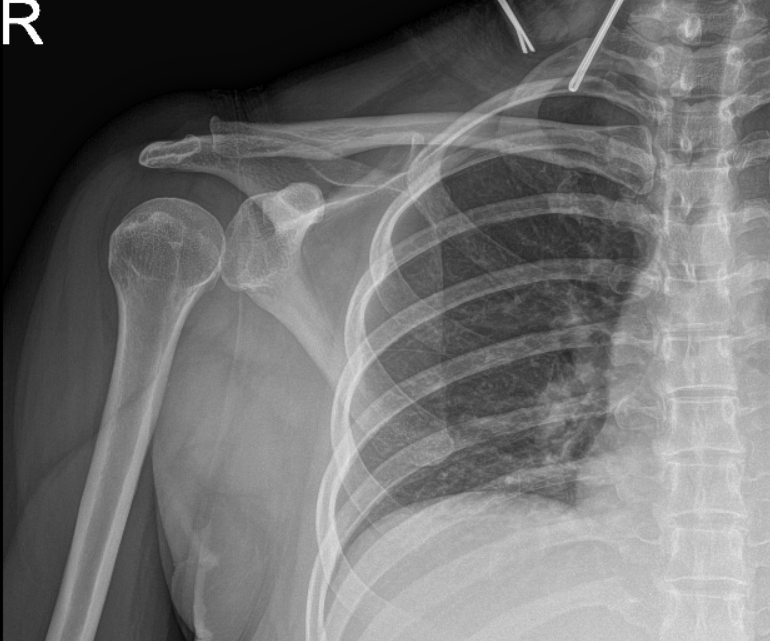

The patient also presented an Xray results and showed normal right shoulder radiographs.

Right shoulder X-ray